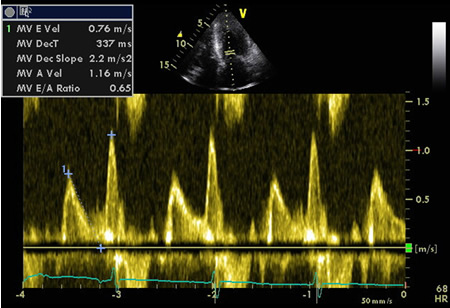

Relaxamento comprometido: fluxo de entrada mitral exibindo inversão de E:A

Do acervo de Dr Jessica Webb; usado com permissão